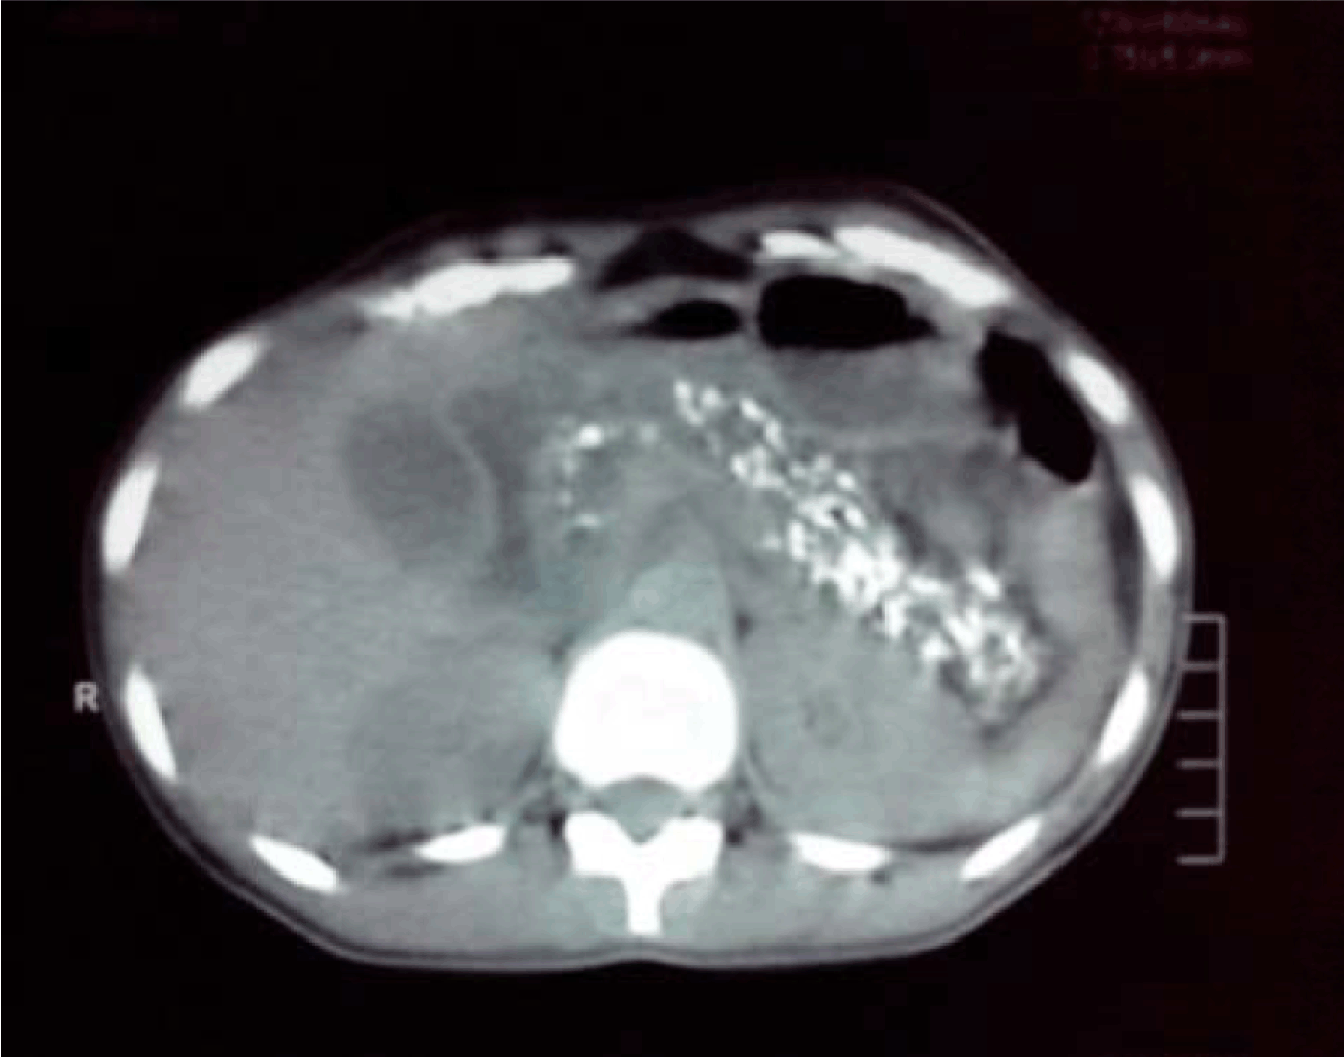

A total of 80 patients were analyzed. Of them 60 were male and 20 were female. The age of the patients varies between 13 to 58 years. The mean age and SD is 37 +10.4 years (Figure 1). Regarding the etiology of chronic calcific pancreatitis, alcohol was associated in 58 patients and 22 patients were considered to be tropical calcific pancreatitis. (Table 1). Of the various complications in this group (Figure 2): Ten presented with diabetes mellitus, six presented with exocrine insufficiency, splenic vein thrombosis with fundal varices was seen in three patients. Pseudocyst in the tail of the pancreas was seen in seven patients. Pancreatic ascites was present in three patients and only two of them without head mass presented with jaundice. All the patients underwent CECT scan to look for calcifications and head mass (Figure 3). MRCP was done in two patients who presented with jaundice (Wadsworth syndrome) both of them had a tapering end of the distal CBD in the absence of head mass (Figure 4). Upper gastrointestinal endoscopy and portal venous Doppler was done for all patients. Only three patients who had splenic vein thrombosis on portal vein Doppler had fundal varices on endoscopy and diagnosed as sinistral portal hypertension. All the patients underwent Frey procedure as already described, amount of tissue cored was measured in grams. Average tissue coring done in the 80 patients is 3.8 grams (Figure 5A-E).

Figure 3: CECT abdomen showing diffuse calcification in head and body.